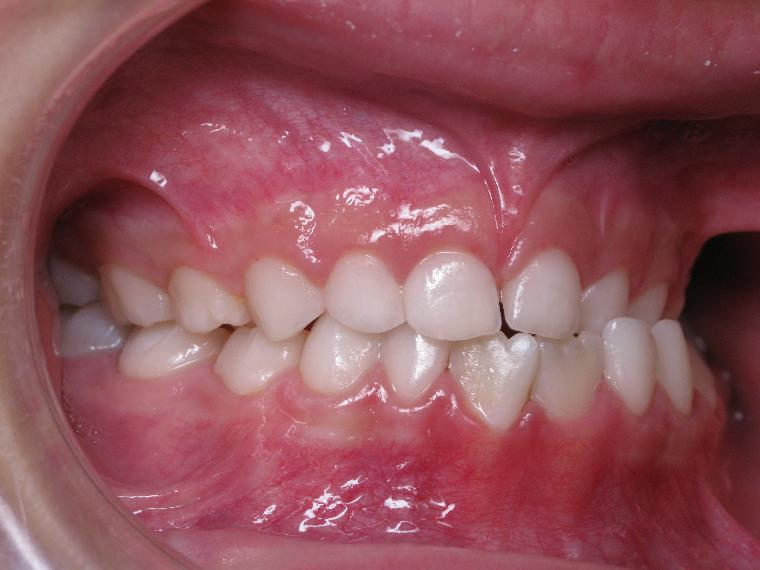

inversion des dents posterieur cote gauche

appareillage mobile pendant 9 mois